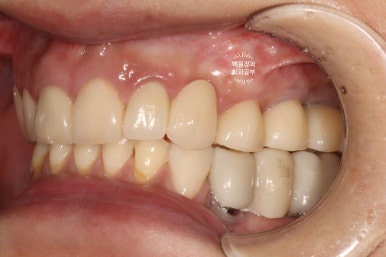

처음에 계획했던 5개의 어금니 임플란트와 3개짜리 지르코니아 브릿지 완성 후 정면 사진입니다.

아주 깔끔하게.... 정말 이상적으로 완성된 것을 보실 수 있습니다.

양 옆모습을 돌려서 보시면 위어금니와 아래어금니가 확연히 비교되는 것을 보실 수 있을겁니다.

일단 치아 경계 잇몸에 은색으로 보이는 부분 없이 깔끔하게 마무리가 되었습니다.

색상도 무조건 하얗지만은 않아서 개인적으로 더 자연스러워졌다고 봅니다.